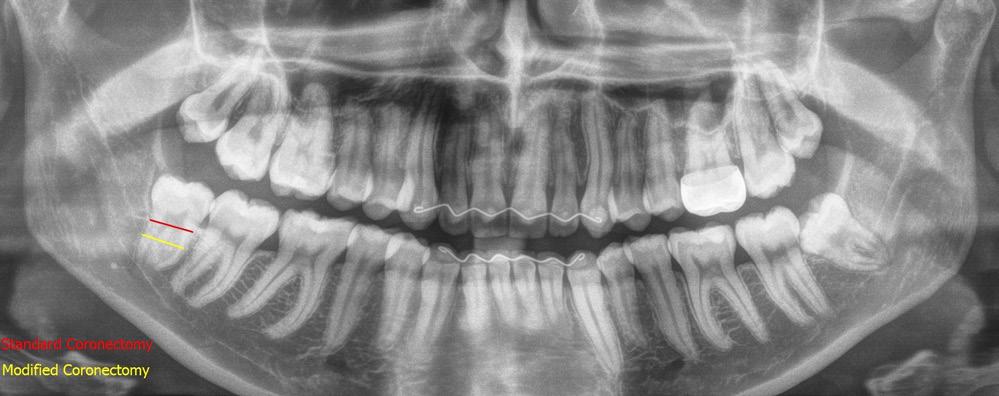

The technique of coronectomy as described by Pogrel6, where the tooth is sectioned at the CEJ is being used more widely within the profession since then. The modified coronectomy is a variation of the technique where the crown is sectioned at or below the furcation with further reduction of the height of the roots. This aims to allow a good skirt of alveolar bone around the roots and the advancement of the buccal flap to achieve primary closure for good postoperative bone and soft tissue healing.

A standard coronectomy technique for removal of RL8 tooth was carried out. Lingual periosteum was not reflected to avoid lingual nerve injury. Following sectioning and trimming of the tooth until the cementoenamel junction (CEJ), there was insufficient soft tissue to achieve primary closure of the socket.

To achieve good primary closure, it was decided to modify the procedure and trim the roots up to the furcation to ensure a sound collar of alveolar bone and advance the buccal flap. This modification helped significantly during primary closure of the socket. LL8 tooth was removed completely as the roots became loose as well as UR8 and LU8. The post-operative phase was uneventful, and she recovered well (Fig 4).

SC: Standard coronectomy MC: Modified coronectomy